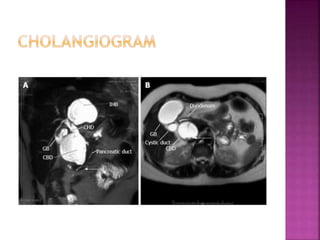

 Congenital dilatation of the biliary system

 Etiology – Congenital abnormality of the

junction of the biliary and pancreatic ducts

which may allow reflux of pancreatic juice

into the biliary tree causing weakening of the

wall of the biliary tree with subsequent

dilatation

 Pain in right hypochondriac region, jaundice and

palpable lump is considered diagnostic

 Features of cholangitis , septicemia, biliary stones

 Eventually – malignancy

 Diagnosis – USG Abdomen , HIDA scan

 Confirmation of pattern of excretion of the bile and

confirmation that the cyst is visible on sonography

in continuation with the biliary tree.

• 46.

 Congenital dilatationof the biliary system  Etiology – Congenital abnormality of the junction of the biliary and pancreatic ducts which may allow reflux of pancreatic juice into the biliary tree causing weakening of the wall of the biliary tree with subsequent dilatation

• 47.

 Pain inright hypochondriac region, jaundice and palpable lump is considered diagnostic  Features of cholangitis , septicemia, biliary stones  Eventually – malignancy  Diagnosis – USG Abdomen , HIDA scan  Confirmation of pattern of excretion of the bile and confirmation that the cyst is visible on sonography in continuation with the biliary tree.